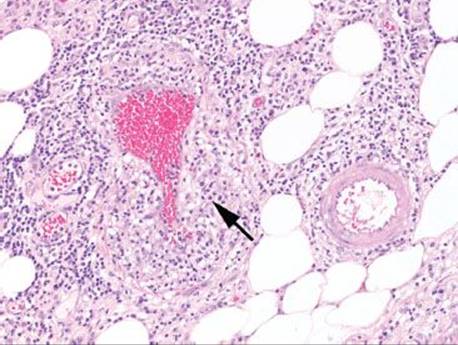

Figure 4.69 Ischemic colitis pattern, venulitis in Behçet disease. One should always consider vasculitis as a cause of ischemia or ulceration, but take care to look in areas away from ulcers. This example shows a striking lymphocytic venulitis (arrow) that has obliterated the small vein. It is easier to search for small muscular arteries (pictured top right) and then look in the proximity for the paired vein.

Which came first, the chicken or the egg? Although underlying vasculitis can certainly cause mucosal ischemia, vascular thrombi and inflammatory changes can be secondary to ischemic-reperfusion injury. As a result, primary vascular injury should be evaluated in areas not directly subjacent to ischemia or ulceration, and close clinical, radiologic, and serologic correlation should be performed in cases suspected of primary vasculitis (Fig. 4.69–4.72).